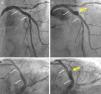

A 45-year-old man with previous history of hyperlipidemia was admitted with an inferior myocardial infarction requiring implantation of a drug-eluting stent (DES) in the mid right coronary artery. One year later he presented with angina and angiography demonstrated severe in-stent restenosis (ISR). After lesion predilation with a cutting balloon, a 3.5 mm×18 mm bioresorbable vascular scaffold (BVS) (Absorb, Abbott Vascular, CA) was implanted and postdilated up to 24 atm using a non-compliant balloon, with an excellent final result (Figure 1A). Optical coherence tomography (OCT) confirmed appropriate expansion and apposition of the BVS, with a minor intimal dissection at its proximal edge. The patient remained completely asymptomatic, but at nine months underwent a scheduled angiography that revealed moderate ISR of the BVS. In addition, a coronary artery aneurysm (CAA) was detected immediately proximal to the BVS location (Figure 1B). OCT showed the presence of an heterogeneous pattern of neointimal hyperplasia (Figure 2A and B) and confirmed the origin of the CAA immediately proximal to the BVS edge (Figure 2C and D). Interestingly, a minor rupture with intraluminal thrombus was also detected at the origin of the CAA. As fractional flow reserve was 0.79 and instantaneous wave-free ratio was 0.93, and the patient denied any symptoms, the lesion was not treated. During follow-up, a stress echocardiogram was negative.

(A and B) Angiographic result after implantation of a bioresorbable vascular scaffold (BVS) in the proximal left anterior descending coronary artery (small white arrows indicate the ends of the BVS); (C and D) at nine-month follow-up formation of a coronary artery aneurysm (yellow arrow) is demonstrated in the mid segment of the BVS.